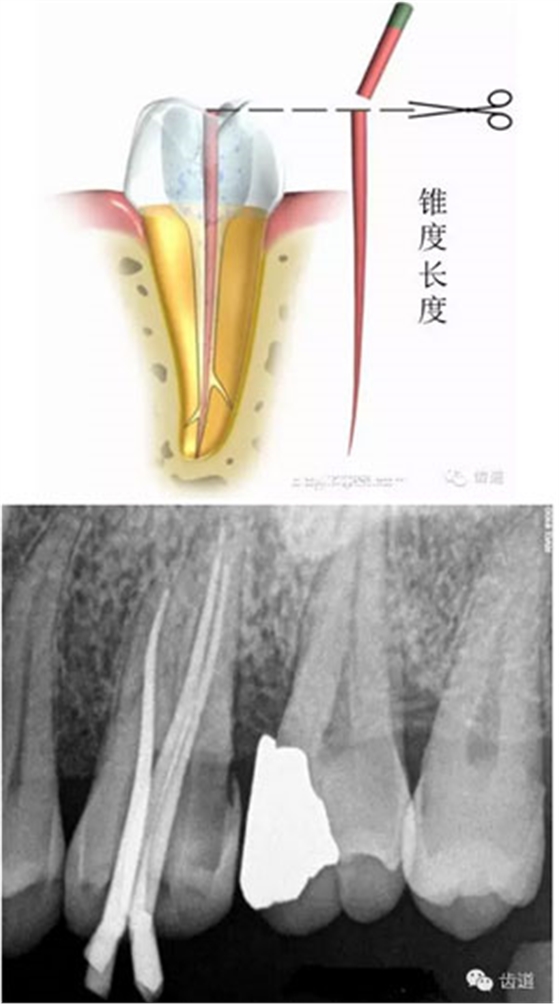

試尖,使其達(dá)到工作長度,修整超出根尖孔的多余牙膠尖。選擇合適的牙膠主尖,距根尖0.5-1mm處卡住即可;或者選擇預(yù)備時最后一支銼相同型號的牙膠尖,尖端需剪去0.5mm。

根據(jù)根管大小選擇匹配攜熱加壓頭,攜熱加壓頭尖部據(jù)根尖5mm左右即可,用橡膠定位圈定位。同理,選擇合適的垂直加壓器